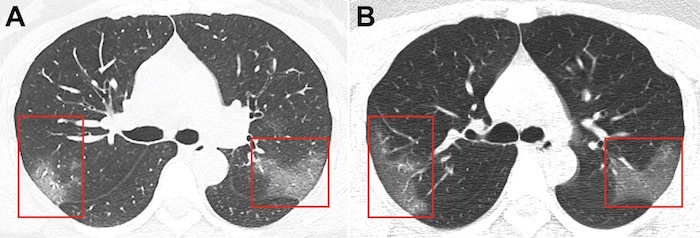

Un grupo de investigadores del Primer Hospital de la Universidad de Lanzhou (China) ha publicado este viernes dos radiografías de tórax de una mujer infectada por el coronavirus 2019-nCoV en la revista Radiology. La segunda—tomada al cabo de 3 días—mostró los signos del avance de la enfermedad.

La mujer, de 33 años, trabaja en Wuhan y viajó a la ciudad de Lanzhou un día antes de que empezaran sus síntomas. Transcurrido un tiempo, tuvo que acudir al hospital, ya que para ese momento llevaba 5 días con tos y 39 ºC de fiebre. Los médicos detectaron que la paciente, que se mantiene en el anonimato, presentaba una respiración “áspera” y un recuento bajo de glóbulos blancos: signos de la infección.